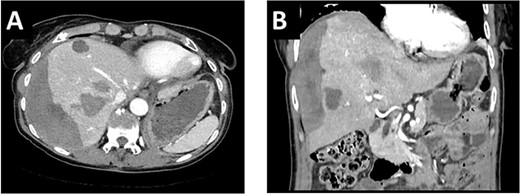

A 65-year-old, otherwise healthy patient was diagnosed with a moderately differentiated adenocarcinoma of the sigmoid colon with a KRAS mutation. Laboratory results showed an elevated CEA of 69 ug/l. Staging of the liver showed multiple liver metastases in all segments with 10 lesions in the right and 8 in the left hemiliver (Fig. 1A).

(A). In the initial pre-chemo MRI of the liver multiple liver metastases in all liver segments could been seen. The largest were in segments II/III (26 mm), V (37 mm) and segment VI (40 mm). (B) After 12 cycles of chemotherapy a size reduction of liver metastasis up to 12% could be achieved. The metastases in liver segments V and VI decreased from 43 to 38 mm and from 37 to 33 mm.

After multidisciplinary tumor board (MDT) discussion, neoadjuvant chemotherapy with six cycles of FOLFOXIRI and Bevacizumab followed by liver-first approach was decided. Restaging after 3 months showed stable disease of the CRLM, therefore, chemotherapy was continued. After 12 cycles, restaging revealed a size reduction of 12% of the CRLM (Fig. 1B). CEA decreased from 69 to 6.1 ug/l. The patient was then admitted to our department for the evaluation of a curative intent CRLM resection. The radiological work-up revealed three remaining metastases on the left- and seven on the right hemiliver. Volumetry illustrated a standardized FLR (sFLR) for a right hemihepatectomy of 30%. In an MDT and the patient was deemed amenable to ALPPS surgery due to the marginal sFLR, bilobar metastases and exceptionally good performance status. Preoperative liver function tests showed normal liver function (LiMAx 450 mcg/kg/h, cut-off >315 mcg/kg/h and ICG R15: 4.0%, cutoff <12%). Although liver biopsy is not routinely performed before ALPPS, MDT recommended a biopsy of the healthy liver to rule out chemotherapy-associated steatohepatitis after 12 cycles of FOLFOXIRI and Bevacizumab in order to ensure a safe liver resection. The biopsy showed signs of subacute hepatocyte demise without fibrosis or cirrhosis. The day after the liver biopsy, the patient collapsed and was admitted to the emergency department of another hospital. CT scan showed a large intrahepatic hematoma (Fig. 2) without active bleeding probably secondary to the biopsy procedure. Due to a hemoglobin drop of 12 g/l a day later and the enlargement of the hematoma in follow-up CT scan, the patient was admitted to angiography, which showed several subcapsular liver bleedings, therefore the right hepatic artery was embolized. Luckily, an accessory right hepatic artery arising from the superior mesenteric artery was present. This enabled us to stay on track with the ALPPS procedure as the right hemiliver would be otherwise without any blood supply (Fig. 3). In synopsis of those findings, the operation was scheduled.